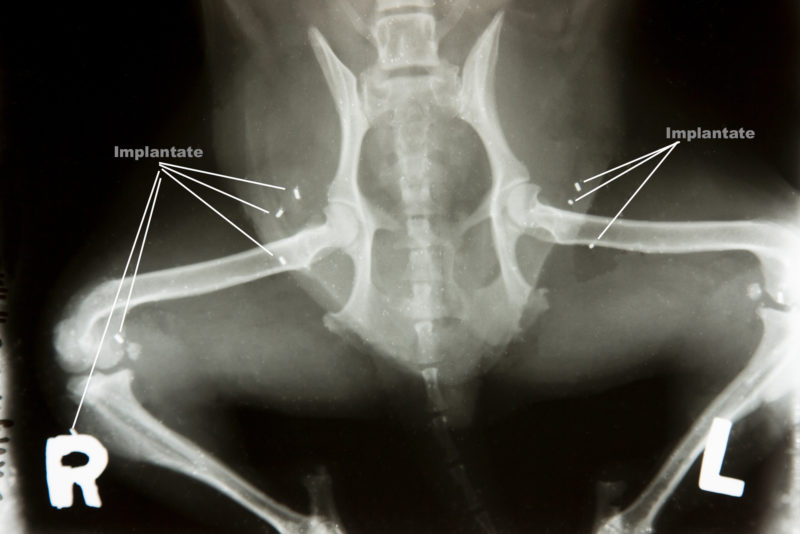

Als Leika eine Woche später erneut vorgestellt wurde, stand sie hinten rechts nur noch auf der Zehe. Ein Anwinkeln des Beines verursachte so starke Schmerzen, dass sie schrie. Zusätzlich wurde ein beginnender Muskelschwund (Atrophie) festgestellt. Die Röntgenaufnahme der betroffenen Region gab diagnostische Sicherheit: Hüftgelenksdysplasie (HD), bei der der Oberschenkelknochen Reibungen an der Hüftgelenkspfanne zeigte. Dieses Krankheitsbild stellt eine eindeutige Indikation für eine Goldimplantation dar, die ich der Halterin dringend nahelegte. Der Eingriff fand im September 2016 statt. Dabei wurden insgesamt 19 Goldstücke um den Oberschenkelkopf, an Wirbelsäule, Kniegelenken, Ellbogen sowie Vorder- und Hinterpfoten eingesetzt.